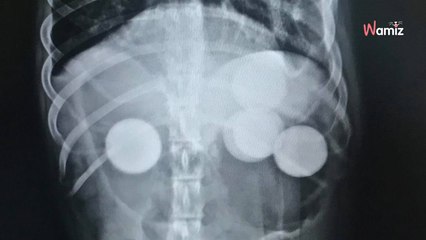

Après un accident de la circulation, ce chien a eu un réflexe de survie qui a montré sa grande intelligence.